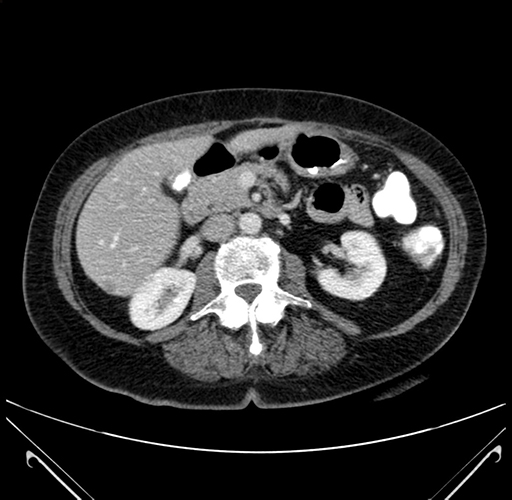

Pre-Chemo: Axial Venous